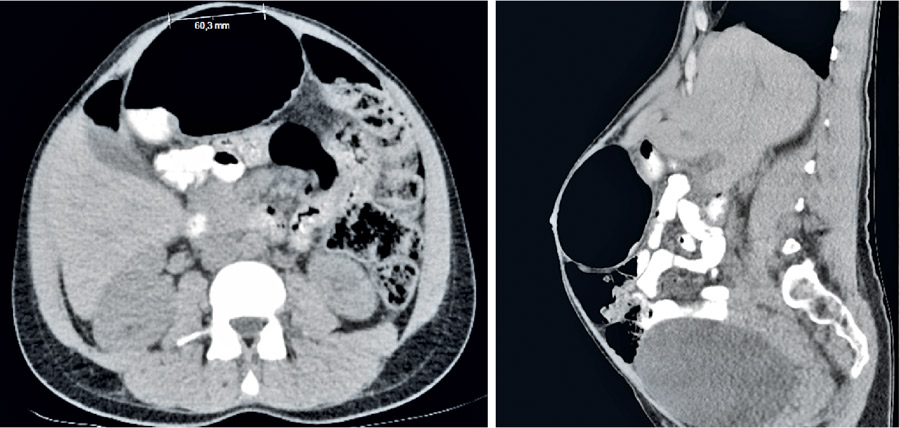

Figur 2. Rektusdiastas och uttänjd rektusmuskulatur under krystning (dator­tomografi), bilden till höger från sidan.